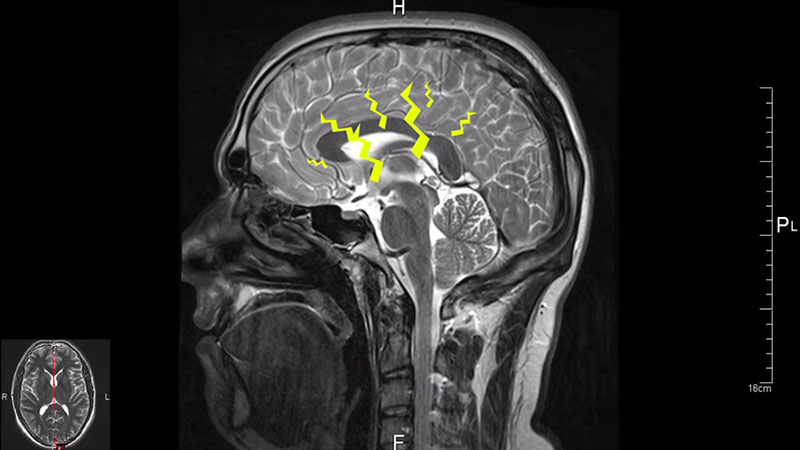

ภาพจาก Vsauce